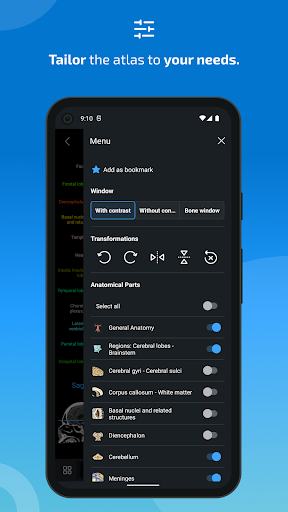

- Pilih label anatomi berdasarkan kategori

- Anda sekarang dapat menyembunyikan struktur satu per satu (tombol baru di dalam tampilan deskripsi) dan menampilkannya lagi di menu sebelah kanan